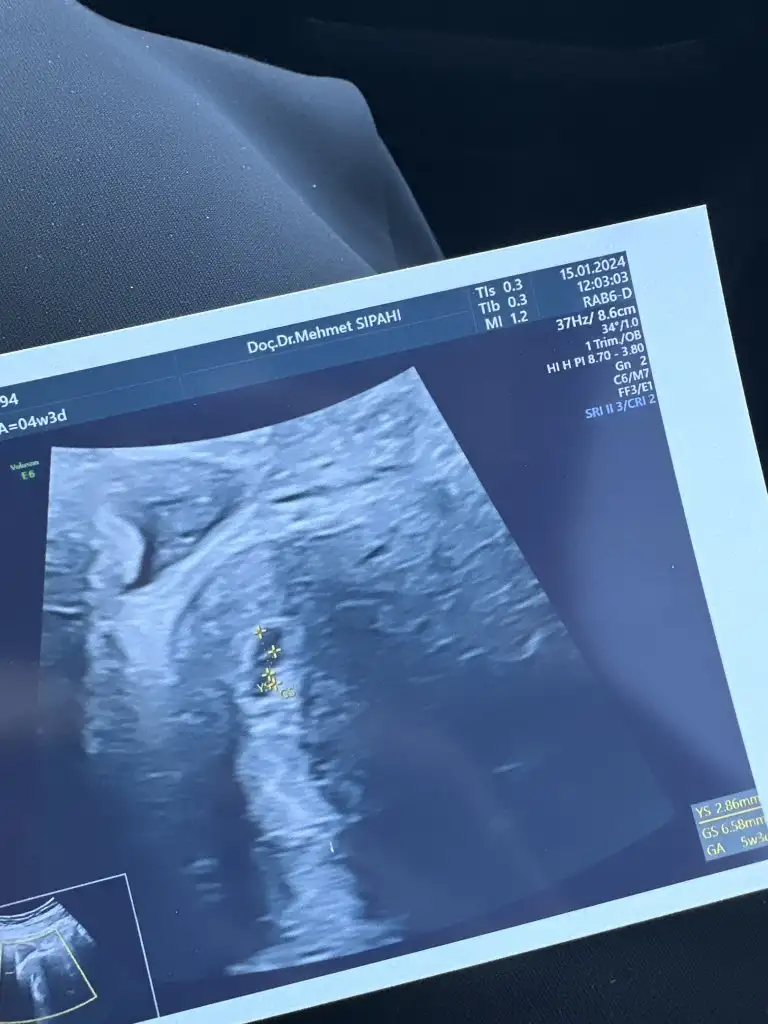

Evet aynı gün kan vermiştim 786 çıkmıştı. 3gun sonra tekrar gittiğimde kese daha net, büyüktü. Sizde daha iyi görünürÇok sağolun keseyi bile görememekten tedirginim bebeğimi görürsem mutluluktan ağlayabilirmBir de şey sorucam 5+3 teyken görüldüğünde beta hcgnizi hatırlıyor musunuz betayla ilgisi var mı bilmiyorm ama hesaplamam göre 8900 civarında olucak yarın betam